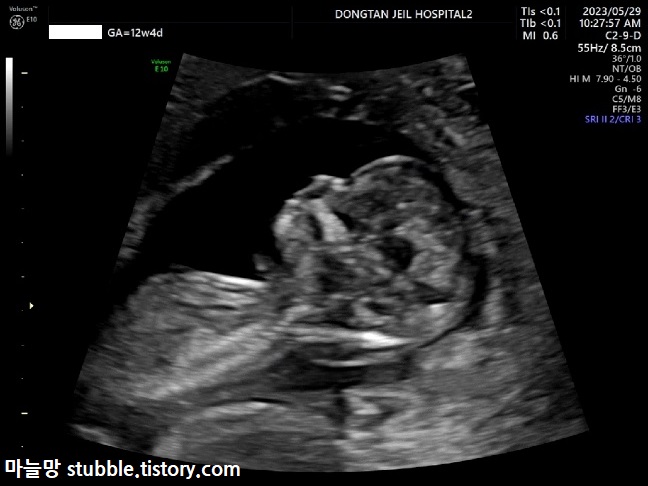

태아 목투명대 (NT) 검사입니다. 보통 아기 CRL(머리에서 엉덩이까지 길이) 4.5cm 이상일때 11주부터 13주 사이에 검사를 하고, 목투명대 길이가 3mm가 넘으면 다운증후군등의 염색체 이상일 확률이 있을 수 있다고 하여 하는 검사 입니다.

계속 엎드려서 아래쪽을 보고 있는 우리 아기입니다.

두근두근!! 우리 아기의 목투명대 길이는 1.62mm가 나왔으므로 안정권입니다.

또렷해진 사람의 모습! 많이 컸지요?

이번에는 얼굴 쪽 옆모습을 잡았습니다.

얼굴이 거의 사람의 형태입니다.